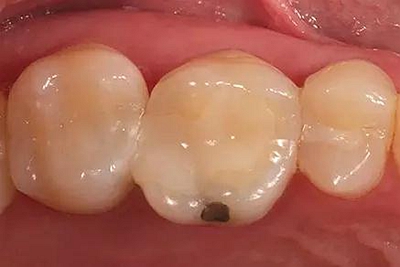

步驟1 原始狀況

16牙位牙齒牙合面觀.

牙齒經(jīng)過根管治療且充填修補,需要重新修復。